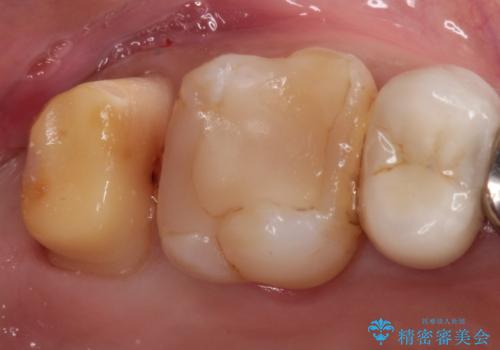

- 定期検診にて虫歯を見つけ、メタルボンドクラウンにて修復補綴治療を行なっております。

歯肉縁下まで虫歯が進行していたため歯周外科を併用して治療を行なっております。

メタルボンドクラウンは内側に金属のフレーム、外側にセラミックを使用した被せ物です。